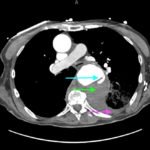

The patient’schest X-ray revealed a prominent mediastinum and opacification in the left middle and lower lung fields. The CT showed an aortic aneurysm extending from the thorax to the abdomen with rupture near T7 (blue arrow). It also showed periaortic hemorrhage with active extravasation (green arrow) likely secondary to a penetrating ulcer and bilateral pulmonary opacities concerning for hemothorax (pink arrow).